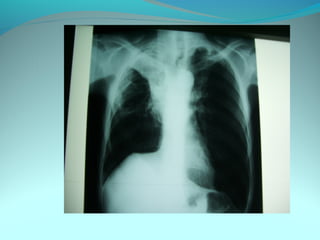

Opacité latéro_trachiale et hilaire droite grossierement arrondie de

6cm de diam dense et homogene

 la limite interne se confend avec le mediastin et la limite externe

nette convexe vers le mediastin

elle confond avec le mediastin évoquant une image mediastinale

Par ailleur on note:

Une surrélevation de la coupole diaph

Un coblement …..

DIAGNOSTIC:

Lymphome H ou NH

Volumineuse ADP tuberculeuse ou sarcoidosique